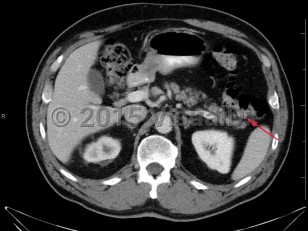

Colonic polyps

Histologically, polyps may be tubular, villous, or tubulovillous. Villous adenomas are 3 times more likely to become malignant than tubular polyps. The likelihood that a polyp contains invasive cancer increases with the size of the polyp. Most polyps remain asymptomatic and are detected during routine screening colonoscopy. Less than 5% of polyps lead to bleeding.